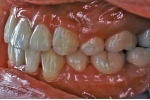

初診時

治療中

マルチブラケット終了時